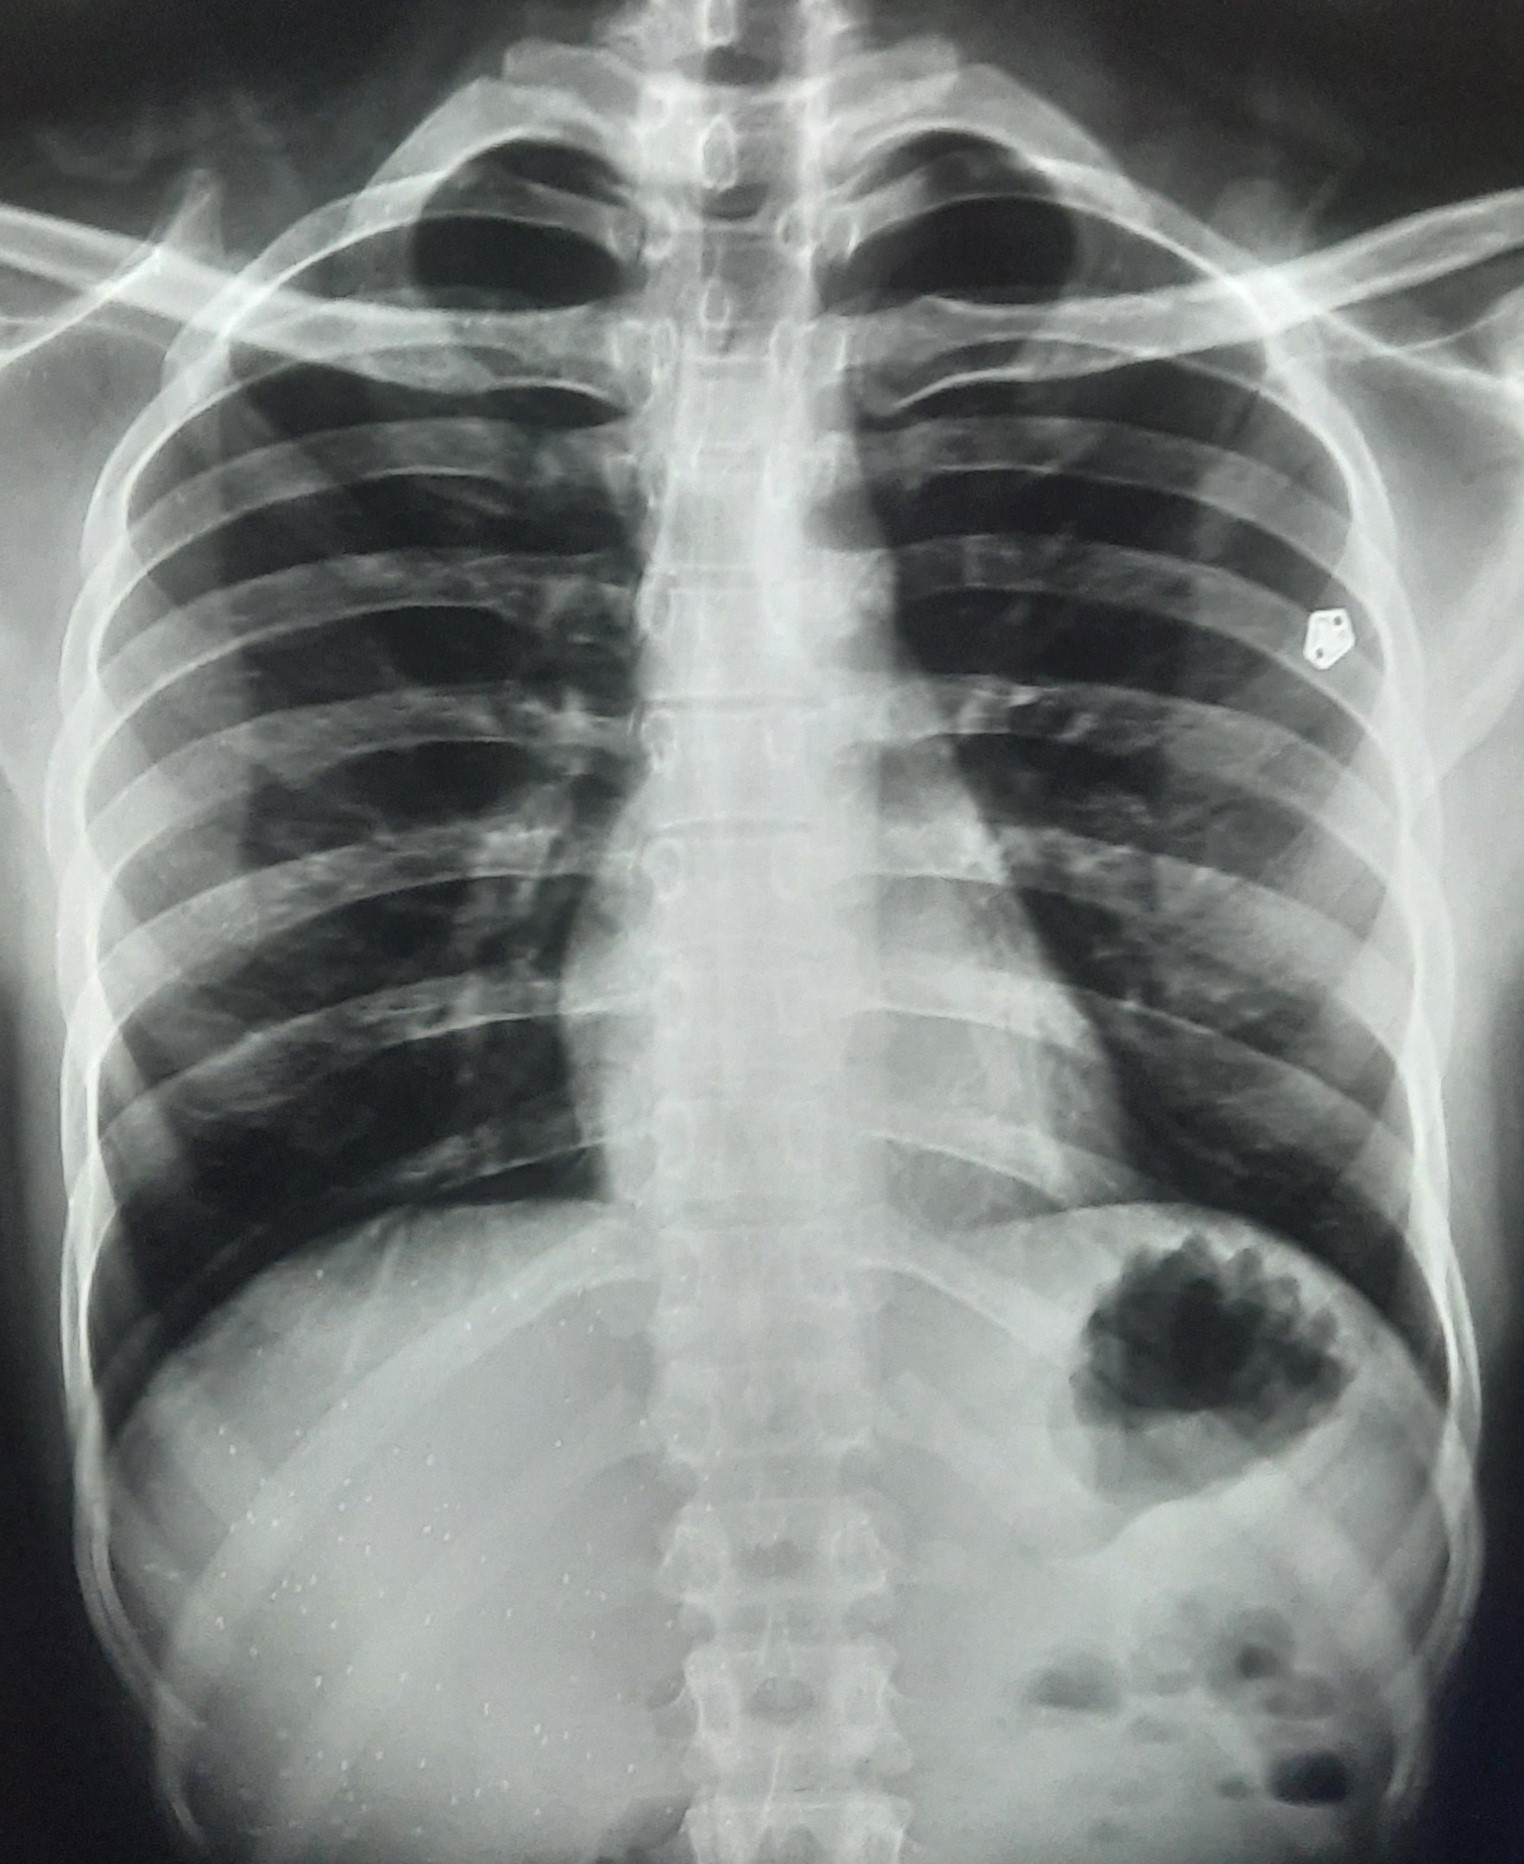

| 297 | IGGMC, Nagpur, Nagpur | P2 | 29-4175 | Sabina Parveen | Consent taken on Paper | 23 Yrs. |

Provisional Diag : PTB Reactivation

Final Diag : ? |

TB Case (Confirmed) | Bilateral Middle Lower Zone Pulmonary TB | Abnormality visible on x-ray |